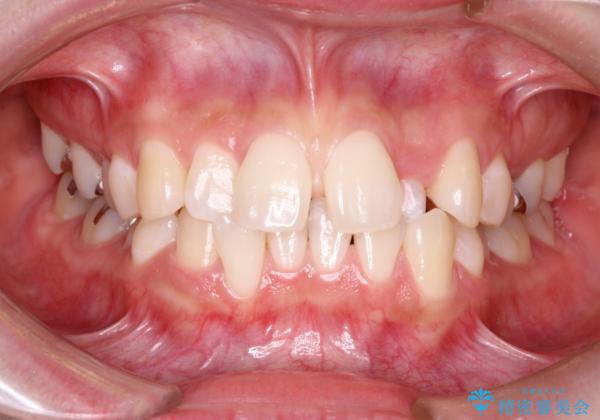

初診時の歯並びの状態としては、上下ともに前歯部の中等度のがたつきがあり、特に左上の前歯が1本内側に入り込んでしまっている状態でした。

また、2mm程度の正中離開がありました。

内側に入り込んでしまっている歯を出してくることに非常に時間がかかりましたが、一度歯を歯茎の方へ押し込みそして前へ出してくる2段階の治療を行いました。